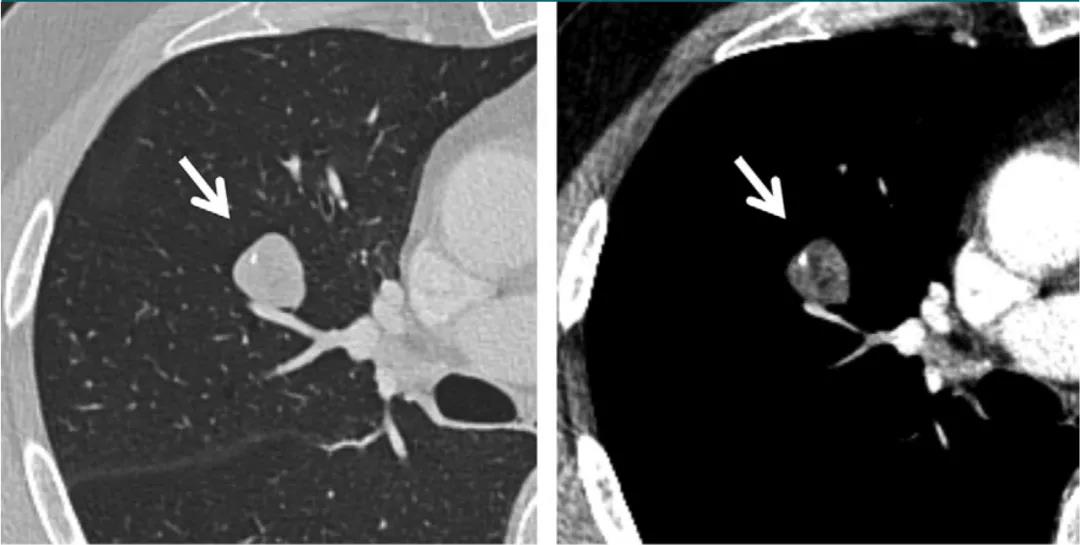

肿瘤医师在患者发现肺部肿块之后、活检之前,可利用专业知识结合影像学特征,对病灶的性质进行预判,这对舒缓部分患者的紧张情绪、提前部署治疗方案等有着重要意义。随着 C...